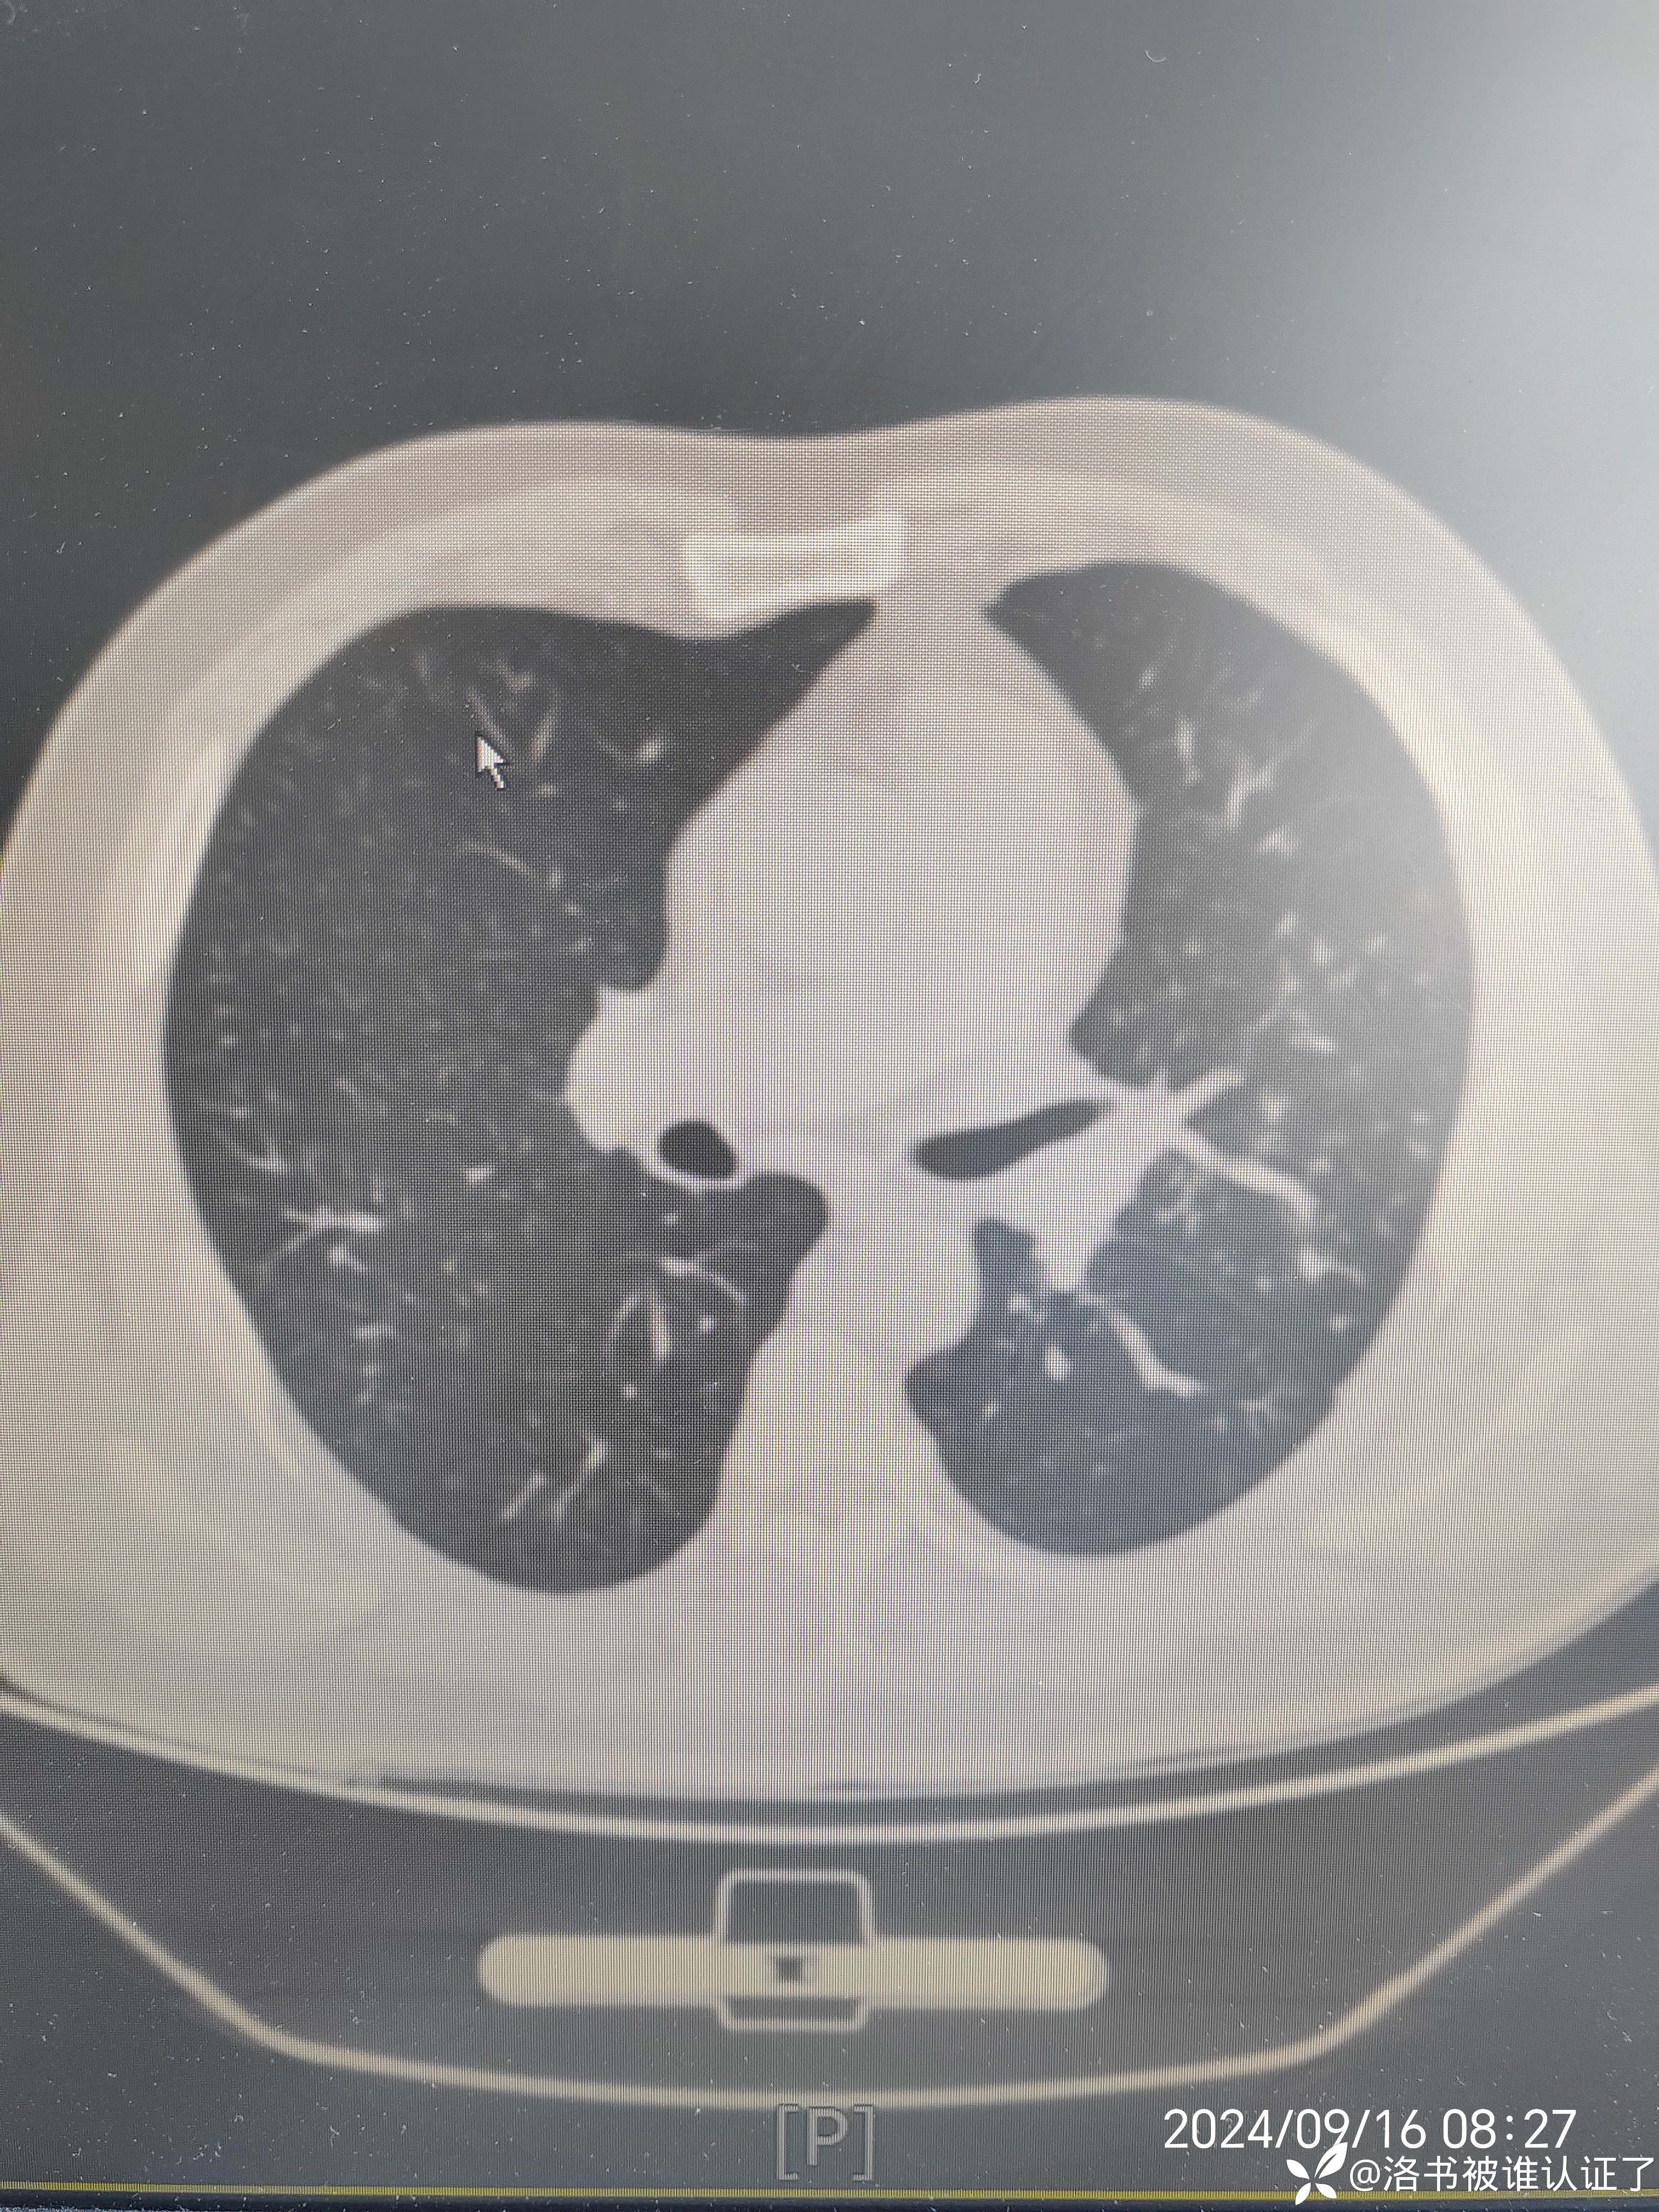

【检查】胸部CT示肺炎。

【临床诊断】:肺炎